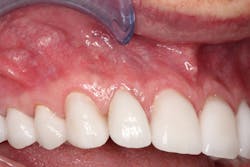

A periodontist completed the crown lengthening surgeries in three separate visits. After healing, the teeth were prepared for crowns, and provisionals (figures 4–6) were placed.

Figure 4: Provisionals

Figure 5: Provisionals

Figure 6: Provisionals